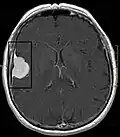

Das bildgebende Verfahren der ersten Wahl ist beim Meningeom heute die Kernspintomografie, da dieses Verfahren den größten Weichteilkontrast besitzt und in typischen Fällen die sichere Diagnose eines Meningeoms ermöglicht. In T2-gewichteten Aufnahmen stellen sich verkalkte Meningeome im Gegensatz zu vielen anderen Tumoren als schwarze Masse (hypointens) dar, die dunkler als das umgebende Hirngewebe ist. Unverkalkte Meningeome können zur Umgebung isointens sein. Von anderen Tumoren unterscheiden sich Meningeome durch ihre Lage auf der Dura mater mit charakteristischen Ausläufern in die Dura (dural tails) und durch eine sehr intensive Kontrastmittelaufnahme. Die Computertomographie kann die Tumorverkalkungen sehr gut nachweisen. Konventionelles Röntgen und Angiographie haben heute nur noch eine untergeordnete Bedeutung.

Typische randständige Lokalisation eines Meningeoms rechts (Kernspintomographie, T1-gewichtet mit Kontrastmittel) -